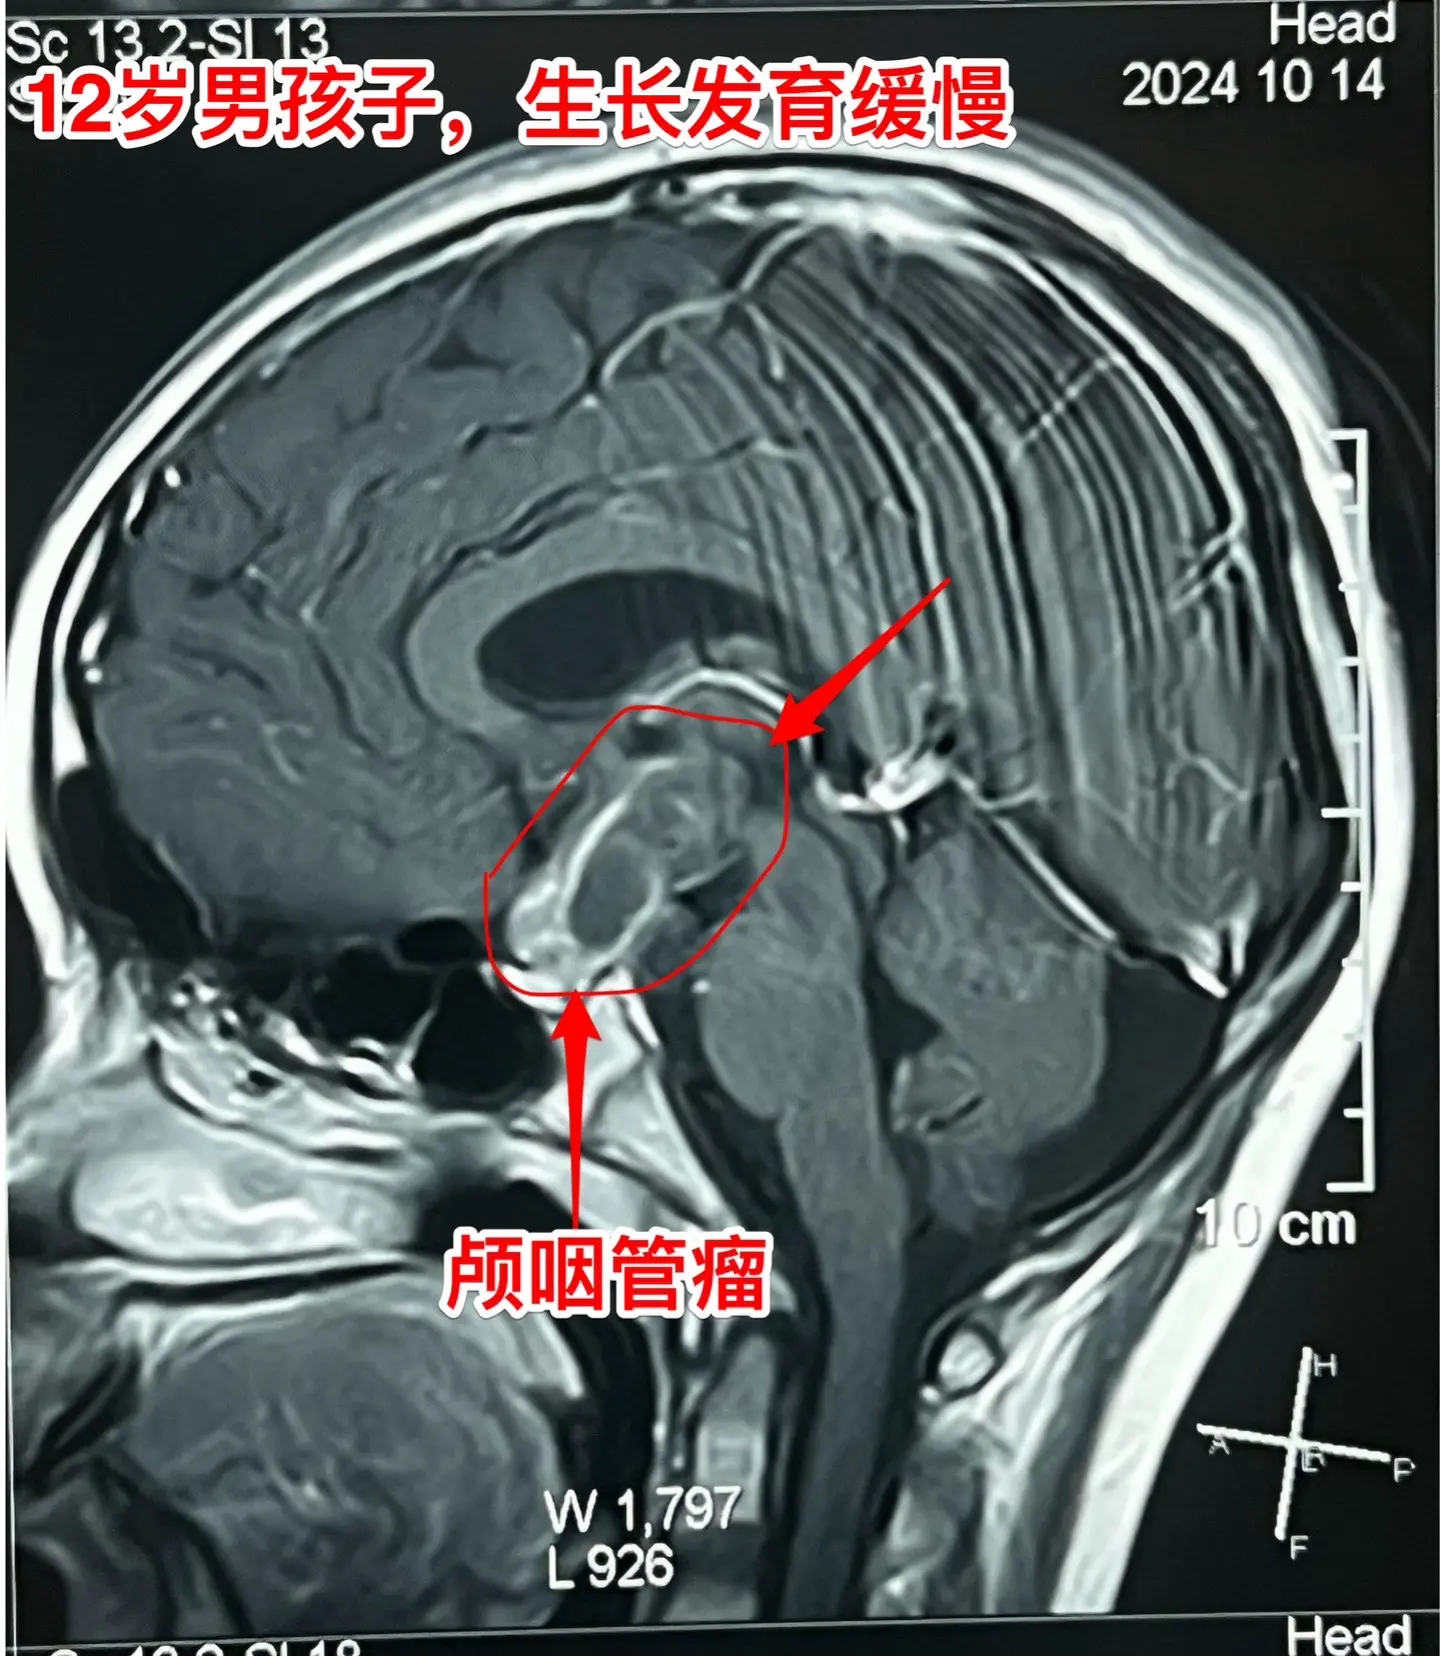

孩子生长发育缓慢,家长要重视。这个12岁的男孩子,在深圳生活,平时爱运动,除了生长发育缓慢之外似乎很“健康”。视力无下降,无头痛症状。 父母观察到孩子的生长发育问题,到医院去检查,发现脑部长了肿瘤,是典型的颅咽管瘤,有钙化。 这个颅咽管瘤是沿着垂体柄内部上下方向生长的,向上长进了第三脑室。这样的颅咽管瘤完全切除的难度比较大,垂体柄也难以保留。 2024.11.15顺利切除肿瘤。手术后患者患者很快就清醒了,从ICU转回来普通病房。希望肿瘤不复发。